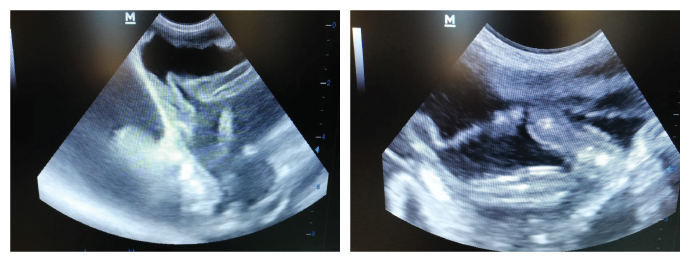

Röntgen ve/veya ultrason dahil fiziksel muayene ile abdominal veya torasik efüzyonları, karın boşluğu içindeki mezenteriyal lenf büyümeleri ve gözdeki değişimleri (ön kamara, iris, retina) tespit etmek mümkündür.